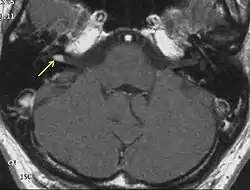

![]() МРТ головного мозга. Невринома слухового нерва указана стрелками | |